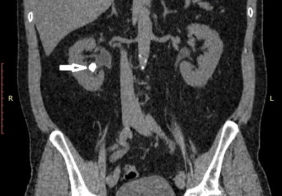

Дроблення коралоподібного каменя через 5 мм. прокол на шкірі

Камінь нижньої чашки 1,8 см.

Камінь миски 2,8 см

Лікування коралоподібного каменю 1 ступеню право, нирки